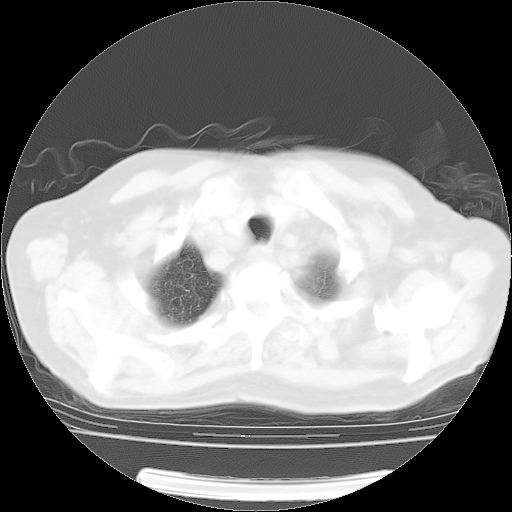

4月14日肺部CT

肺部CT平扫未见异常。